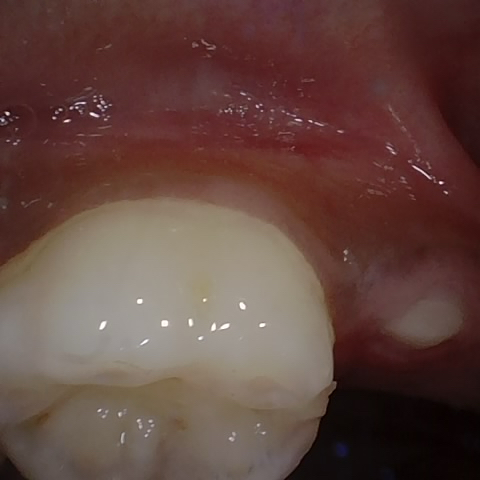

Image 1283 / 1715

NHD35761

Annotated as "Good"

Original Image Rendering Image